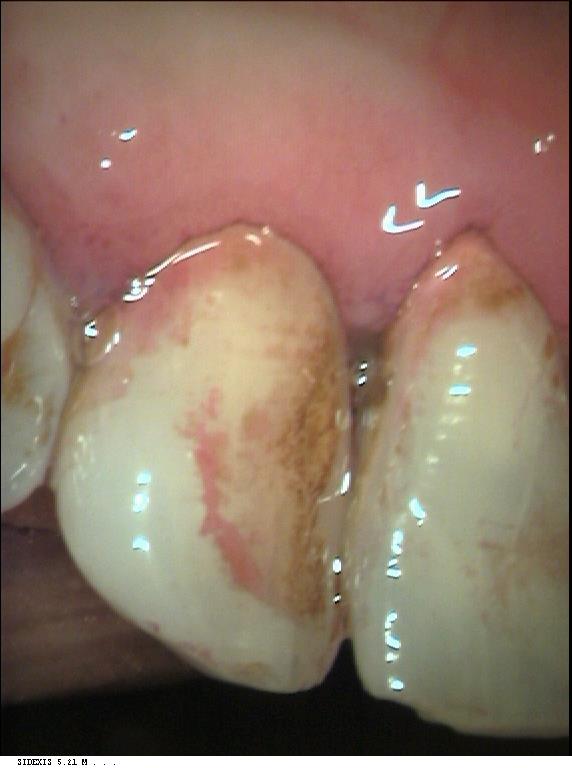

Färbetabletten

Ein bewährtes Mittel zur Darstellung von Belägen auf den Zähnen nach dem Putzen, besonders geeignet zur Motivation von Kindern oder als Selbstkontrolle zur Erlangung einer effektiven Zahnputztechnik. In den Prophylaxesitzungen mit Kindern werden die Ergebnisse der Anfärbung mit der Intraoralen Kamera dokumentiert. Eine sehr anschauliche Kontrolle des Putzergebnisses.